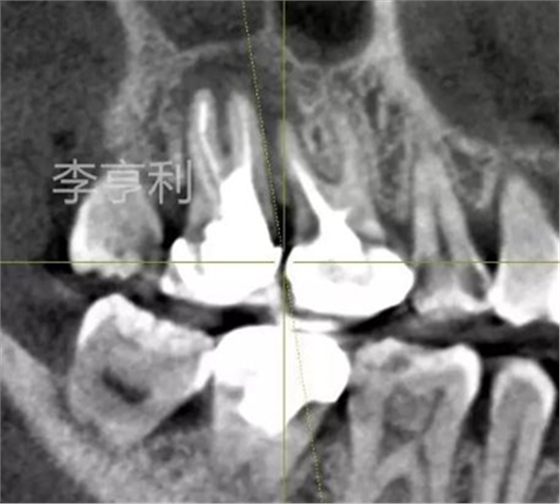

【輔助檢查】: CBCT見17冠部大面積充填物阻射影,接近髓室底,根管內充填物錐度尚可,距根尖均為2mm以內,根尖周大范圍阻射影主要在頰根區(qū)域,波及16的DB根尖區(qū)域,頰腭側骨板完整